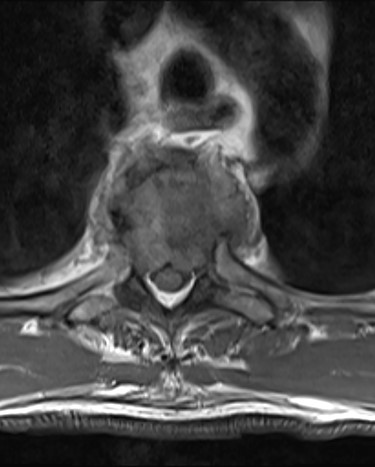

Spinal images are presented in Figs 1–6. Cross-sectional imaging revealed no other neoplastic lesion. He received dexamethasone 10 mg bolus then 4mg four times daily with appropriate proton pump inhibitor coverage. Due to no distinguishable major arterial feeder upon review of the imaging jointly with the neuroradiologist, pre-operative embolization was not attempted. The following morning, he underwent posterolateral right costotransversectomy, ligation of the ipsilateral T4 nerve root, T4 vertebrectomy and insertion of an expandable titanium cage with T1–T7 pedicle screw fixation (Figs 7 and 8). Post-operatively his pain improved to VAS 2/10 and motor power in his left lower limb improved to MRC grade 4/5. The patient was discharged home Day 10 post-admission with physiotherapy.

Sagittal T2-weighted magnetic resonance image (T2W MRI) with T4 metastatic epidural spinal cord compression (MESCC) and a synchronous T10 lytic lesion.